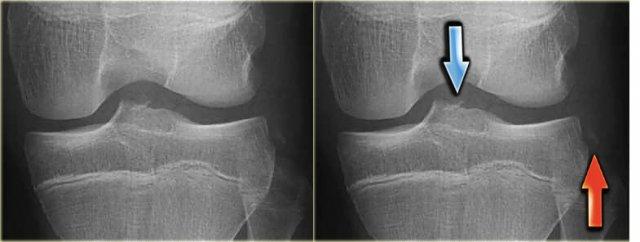

Gãy xương Segond và rách sụn chêm

Gãy xương Segond là tổn thương bong gân (avulsion) của dây chằng bao khớp bên ngoài.

Cơ chế chấn thương là xoay trong kết hợp với lực varus.

Trên phim X-quang, tổn thương biểu hiện dưới dạng một mảnh xương hình bầu dục tách rời khỏi mặt ngoài đầu gần xương chày (hình).

Gãy xương Segond có mối liên quan chặt chẽ với rách dây chằng chéo trước (75-100%) và tổn thương sụn chêm trong và ngoài (66-70%).

Trên phim X-quang, gãy xương Segond có thể dễ bị bỏ sót (mũi tên đỏ).

Lưu ý rằng còn có thêm tổn thương bong gân của dây chằng bên trong.

Tiếp tục xem các hình ảnh MRI.

Bên trái là hình chụp tư thế AP của một bệnh nhân khác.

Kết hợp với gãy xương Segond (mũi tên đỏ), còn có thêm gãy bong điểm bám của dây chằng chéo trước (mũi tên xanh).